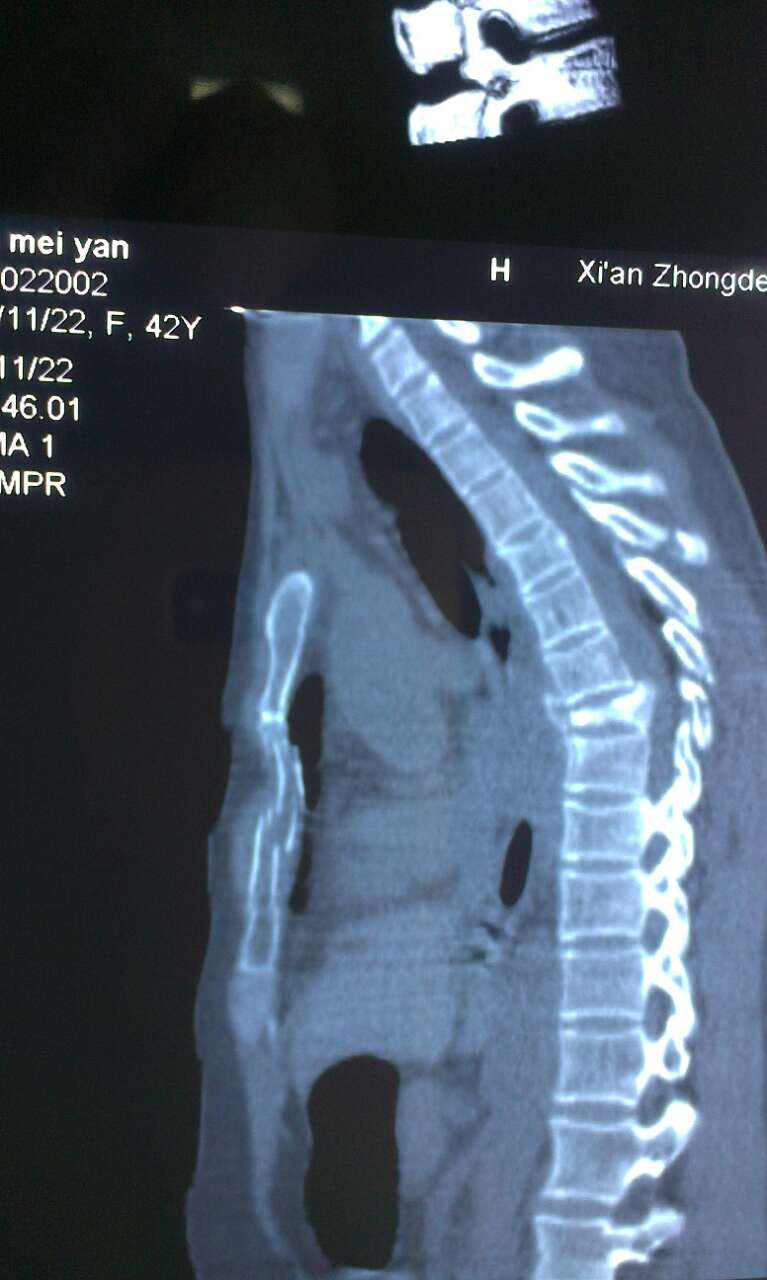

胸骨骨折ct图片大全,手臂骨折ct图片

女42岁,肩胛骨,锁骨,左弟3肋骨,胸骨骨折,胸椎7

ct证实为左侧第二四五肋骨骨折.

曲阳县人民医院双肺严重肺挫伤,多发肋骨骨折病例汇报

胸骨体柄关节脱位

闭式引流术后复查胸部ct,左侧肺不张仍有大量胸腔积液并左侧肋骨骨折